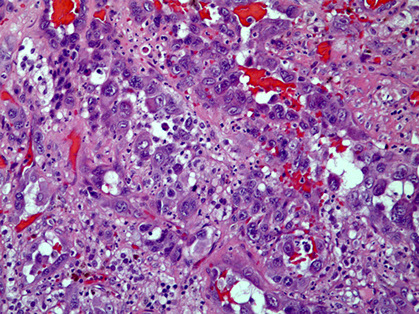

Micro: cords / small nests of round endothelial cells c lots of reddish cytoplasm that expand the vessels as they extend centrifugally from the lumen to the soft tissue in myxoid / mucinous sclerotic background

- blister cells c red cell fragments, which are tumor cells trying to form vascular lumens (similar to what may be seen in lobular breast ca)

-- can have vacuoles in lots of vascular tumors (blister cells are NOT specific for EHE) with plump endothelial cells

- usually does not make well-formed infiltrating vascular channels (like angiosarcoma does); good to distinguish from angiosarc

- lumen filled c necrotic debris, tumor and dense collagen

- round and possibly indented nuclei c intracytoplasmic vacuoles

- minimal mits, atypia or necrosis; though can be significant in small subset

IHC: (+) ERG, FLI1, CD34, CD31; many are keratin positive (CK+)